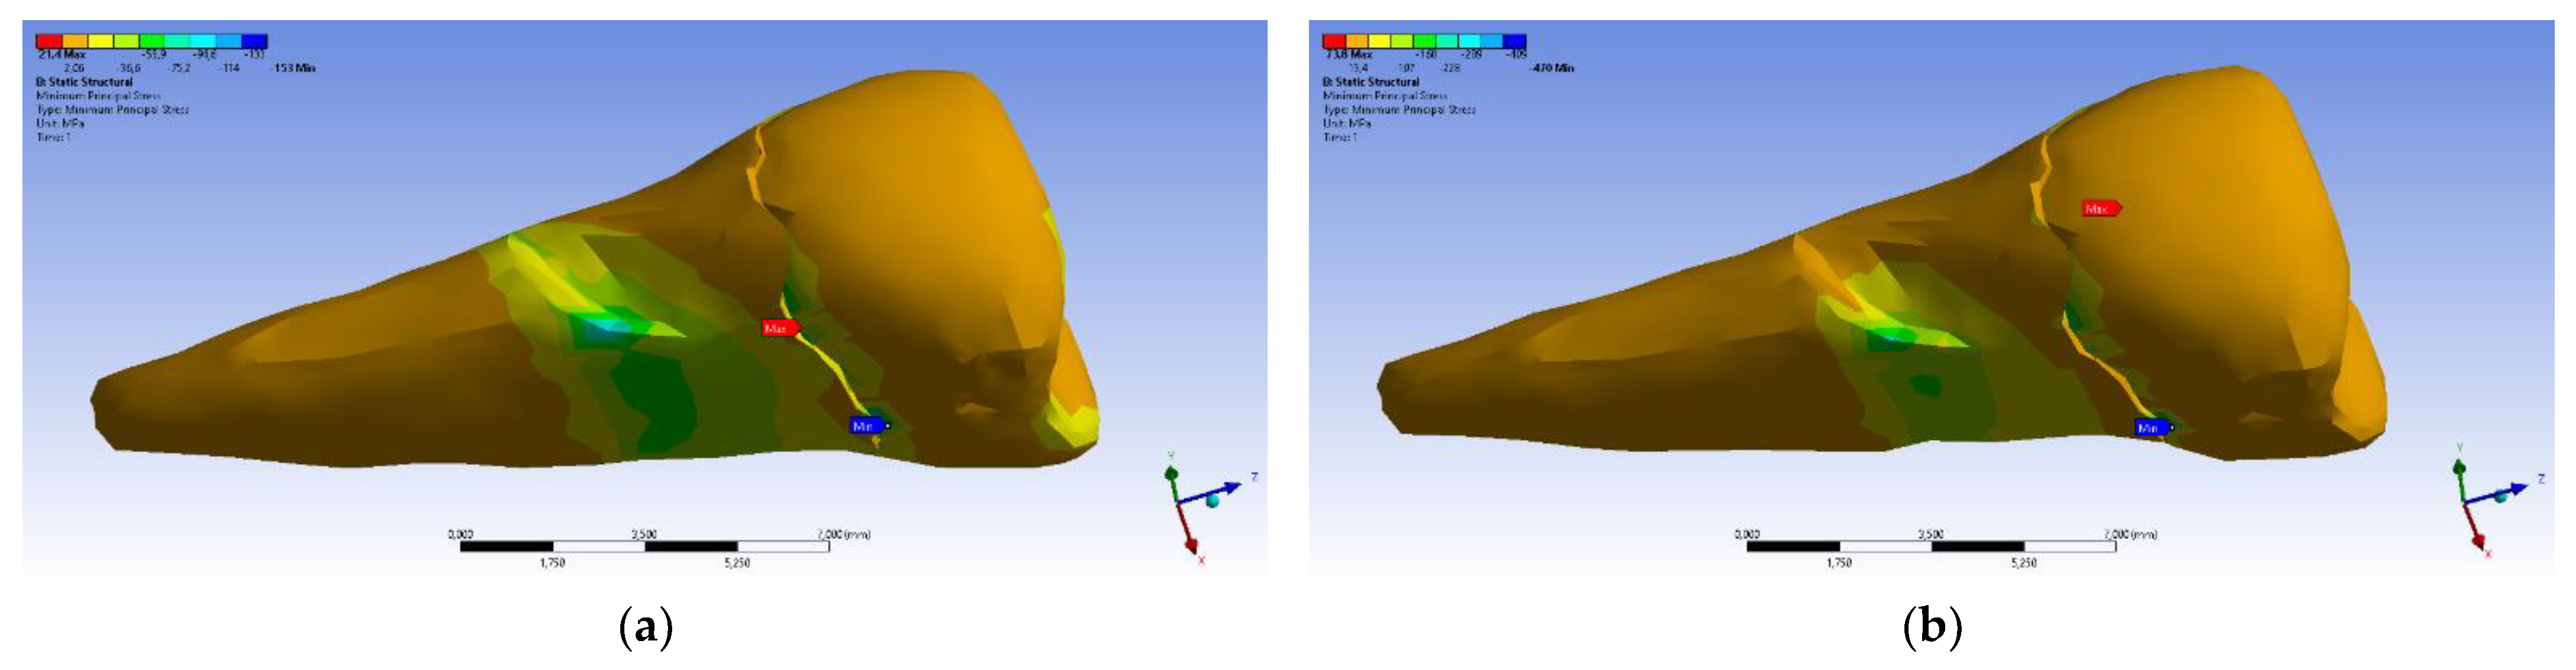

| Total Deformation | Deformation in X Direction | Deformation in Y Direction | Deformation in Z Direction | Equivalent Stress | Normal Stress X | Normal Stress Y | Normal Stress Z | Maximum Main Stress | Minimum Main Stress | Tangential Stress XY | Tangential Stress YZ | Tangential Stress XZ | |

|---|---|---|---|---|---|---|---|---|---|---|---|---|---|

| Minimum | 0 mm | −4.24 × 10−3 mm | −2.52 × 10−2 mm | −1.56 × 10−2 mm | 1.01 × 10−6 MPa | −35.6 MPa | −57.1 MPa | −104 MPa | −15.2 MPa | −152 MPa | −43.7 MPa | −39.6 MPa | −56.3 MPa |

| Maximum | 2.77 × 10−2 mm | 3.57 × 10−3 mm | 6.98 × 10−4 mm | 4.78 × 10−3 mm | 248 MPa | 61.5 MPa | 177 MPa | 72.2 MPa | 195 MPa | 21.4 MPa | 44.2 MPa | 117 MPa | 22.2 MPa |

| Minim. in | Cementum | Cementum | Enamel | Enamel | Cementum | Cementum | Enamel | Enamel | Enamel | Cementum | Enamel | Enamel | Cementum |

| Maxim. in | Enamel | Enamel | Cementum | Enamel | Cementum | Enamel | Enamel | Enamel | Enamel | Enamel | Cementum | Cementum | Cementum |

| Total Deformation | Deformation in X Direction | Deformation in Y Direction | Deformation in Z Direction | Equivalent Stress | Normal Stress X | Normal Stress Y | Normal Stress Z | Maximum Main Stress | Minimum Main Stress | Tangential Stress XY | Tangential Stress YZ | Tangential Stress XZ | |

|---|---|---|---|---|---|---|---|---|---|---|---|---|---|

| Minimum | 0 mm | −6.1 × 10−3 mm | −9.02 × 10−2 mm | −3.99 × 10−2 mm | 1.02 × 10−6 MPa | −112 MPa | −199 MPa | −278 MPa | −65.5 MPa | −470 MPa | −148 MPa | −176 MPa | −178 MPa |

| Maximum | 9.28 × 10−2 mm | 1.83 × 10−2 mm | 1.38 × 10−3 mm | 3.12 × 10−2 mm | 780 MPa | 61.5 MPa | 649 MPa | 304 MPa | 704 MPa | 73.8 MPa | 134 MPa | 370 MPa | 78.6 MPa |

| Minim. in | Cementum | Cementum | Enamel | Enamel | Cementum | Cementum | Enamel | Enamel | Enamel | Cementum | Enamel | Enamel | Cementum |

| Maxim. in | Enamel | Enamel | Cementum | Enamel | Cementum | Enamel | Enamel | Enamel | Enamel | Enamel | Cementum | Cementum | Cementum |